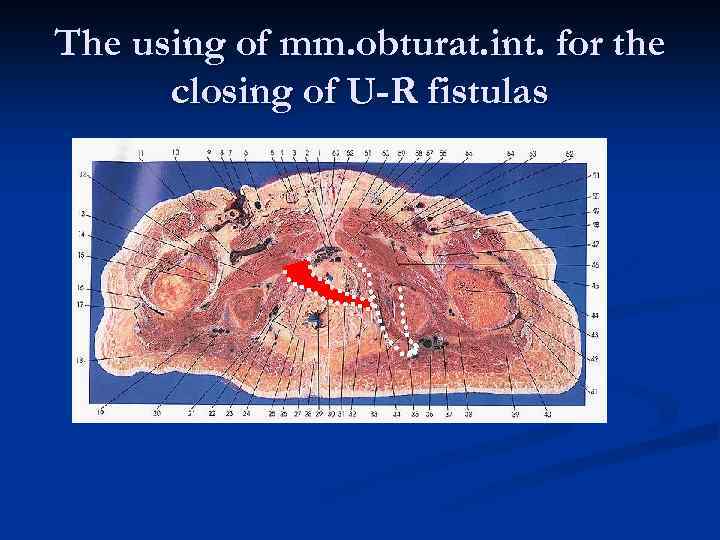

The using of mm. obturat. int. for the closing of U-R fistulas

The using of mm. obturat. int. for the closing of U-R fistulas